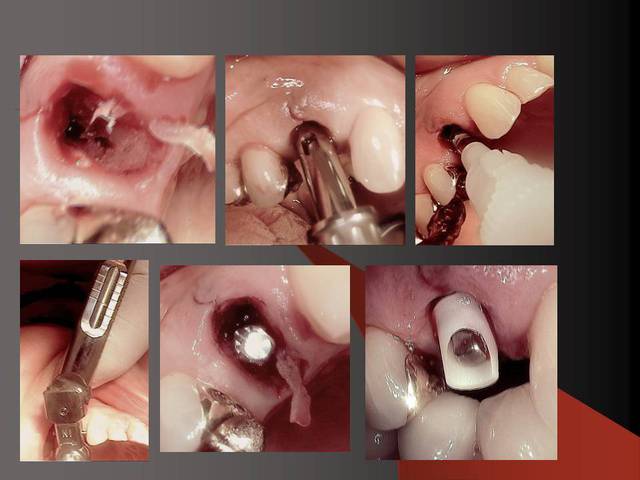

Photos d'un cas d'extraction implantation immédiate, stabilité primaire (de mémoire) assez élevée.. 60/70 N ..démontage du gingiva clips et du shuttle, pilier serré 40N, couronne procera

Merci pour le cas, bien fait. Belle présentation photo.

Le contour gingival est net, belle guérison, c'est à combien de semaine ?

Je vois un peu de ciment sur la radio finale, attention, c'est pas bien pour les tissus.

Oui je sais pour le ciment... j'utilise d'ailleur ce cas et cette radio dans une présentation pour mettre en garde sur le risque au moment du scellement de voir du ciment fuser sous la limite prothétique vers la col de l'implant..galère à éliminer...Personnellement je préfere plutot utiliser des piliers à usiner (maintenant disponibles voir shop online pour photos) au lieu des strandarts meme si il y a deux hauteurs/col implantaire en 1 et 3mm aujourd,hui disponibles..A l'époque de ce cas il n'y avait que les 1 mm et la limite est un "poil" trop profonde.

La pose de la couron nec'est faite 8 semaines apres l'extraction implantation immédiate, la particularité de ce systeme permet de ne pas démonter le shuttle ni la gingivaclip pour l'empreinte..je pense que ca aide bien à la qualité gingivale...radio controle ci jointe